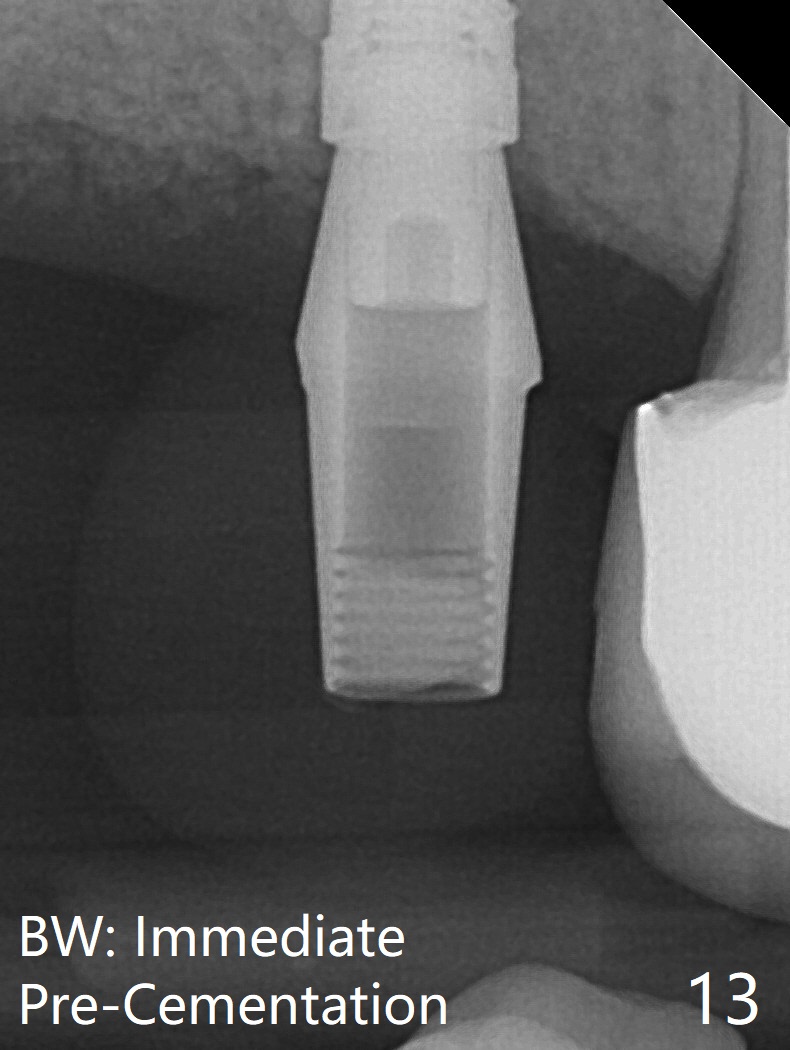

The patient returns for #4 extraction and immediate implant the 1st day clinic reopening after coronavirus lockdown. To reuse autogenous bone for #4 buccal gap closure, delayed implants are also placed at #13 and 14. It is much easier to determine the placement level of the immediate implant (open socket) with guide than that of the delayed ones (flapless) clinically. Immediate postop CT is taken for implant placement level confirmation (Fig.1-3). In fact the autogneous bone is too soft to be packed into #4 socket gaps. It has to be mixed with allograft to be packable. There is oozing when #14 healing abutment is placed. The hemorrhage is severe 4 days postop. The healing abutment is replaced by a healing screw. Hemostasis is achieved when the access is closed with GEM Cap and 4-0 Chromic gut suture. The patient will return for #3 extraction and socket preservation 1 month postop (Fig.4). To prevent postop hemorrhage, a cemented or temporary abutment will be placed at #4 before anesthesia, while .5 or 1.0 cc Augma bone will be placed at #3, covered with collagen plug and acrylic. In fact he cancels the appointment once because of symptom relief and will return 2 months postop. Sticky bone (Fig.5 *) and PRF is used at #3 for hemostasis, while a 5x5.7(3) mm pair (final) abutment is used to hold acrylic dressing in place. The latter remains in place with good oral hygiene 1 month postop (Fig.6 A: abutment). When the acrylic dressing is removed, the socket heals (Fig.7 K: the gingiva between the buccal and palatal sockets when the tooth was removed). The patient returns for impression 4.5 months postop. When the 5x5.7(3) mm abutment at #4 is reseated after cleaning, there is no horizontal gap between the abutment and implant in BW (Fig.8), while there is in PA (Fig.9). When a smaller abutment is seated (Fig.10), there appears to be a horizontal gap, whereas there is no vertical one. The situation is the same with #13 (Fig.11,12). The common denominator is 3.5 mm implant. With suspicion, BW is taken for the implant at #4 immediately before cementation (Fig.13). It appears that the abutment is most likely seated completely. There is no bone loss or screw loosening 4 months post cementation (Fig.14,15). One month later the patient agrees to have 3 lower implants to replace RPD.